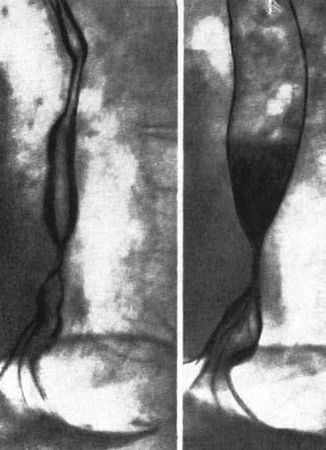

Рис. 28. Рентгенограмма пищевода при короткой пептической стриктуре на почве ГПОД. Пищевод укорочен, часть кардиального отдела желудка находится в заднем средостении. (Приводится по: Е.М. Каган. Рентгенодиагностика заболеваний пищевода. М., 1968)